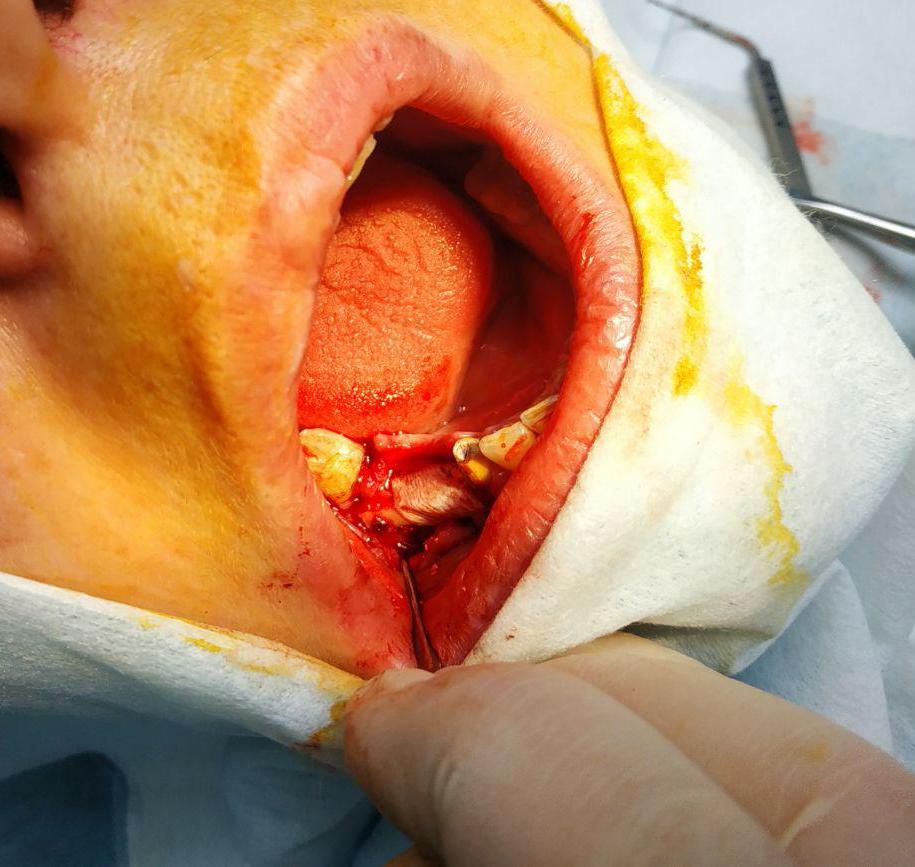

Описание случая: Имплантация при недостаточном объеме кости. Изначальный объем кости был в пределах 3 мм из-за травматичного удаления зубов (выломана картикальная пластинка кости). Для адекватной имплантации минимальный объем - от 6 мм.

Лечение: Принято решение о пересадки ее собственной кости из угла челюсти. Отслоение слизисто-надкостничного лоскута. Забор блока кости в области угла челюсти. Остеопластика блоками + ксенографт. Установка двух имплантов. Наложение швов.

Результаты лечения: Наращивание объема кости до 10 мм. Фиксация имплантов при недостатки костной массы.